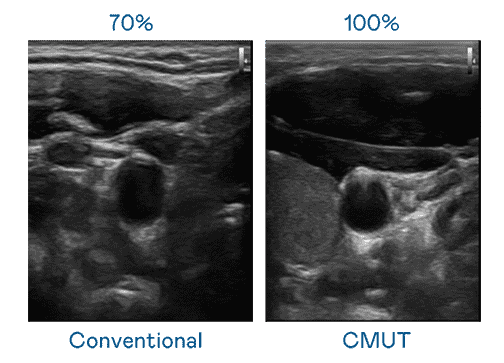

CMUT 技术是一种用电容式微机电元件来产生超音波讯号的技术。。与传统 PZT 压电式技术相比,,,CMUT 频宽增加 30%,,,,更宽频的超音波讯号让影像解析度大幅提升,,,是实现高影像品质医疗超音波扫描、、、、促进精准医疗发展的关键技术。。。

大频宽带来超清晰影像

超音波影像的解析度高低,,首先取决于探头能发出的讯号频宽。。2121非凡 CMUT 可提供高清晰的超音波讯号,,,,提供高频宽、、、高灵敏度、、、、影像纹理细节更高的超音波影像,,,协助医护人员缩短影像判读时间及利用精准的医疗影像进行诊断。。